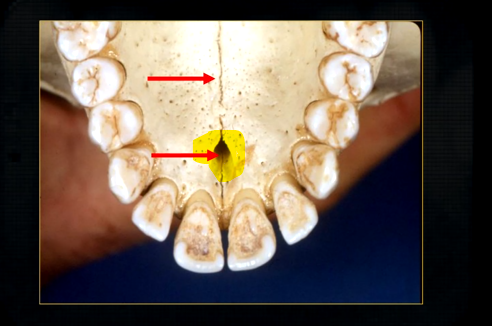

what is this thin line over the palate?

mid-palatal suture

what is this large hole?

naso-palatine foramen

resultant radiographs are always 2d demonstrations of a 3d object - all structures, internal and external will be superimposed on one another

how the anatomy is presented geometrically is dependent on the relative positions of the patient, image receptor and the X ray beam